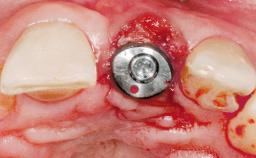

Late Placement of an Implant in a Maxillary Left Central Incisor Site

# of Implants 1

Type of Implants Two-Piece

Placement Protocol Early or late implant placement

Bone Volume Deficient horizontally, requiring prior grafting